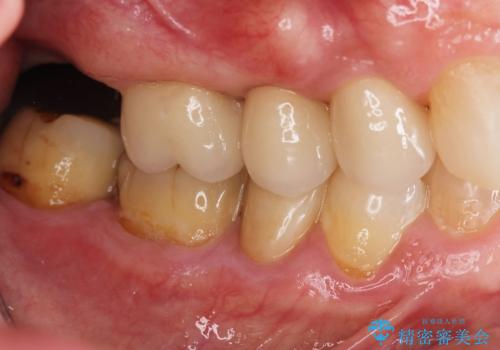

過大な力で折れた失活歯 セラミックブリッジ治療

- かぶせてある歯が数日前からぐらぐらするので付け直してほしい、と希望され来院されました。

かぶせ(以下クラウン)を外してみたところ、神経のない支台となる歯が折れてしまい抜歯を余儀なくされる状況でした。

抜去後の機能回復方法としてインプラント、入れ歯以外の方法を希望されたためブリッジでの咬合機能回復を行っていくこととなりました。

審美的かつ、噛みやすい仕上がりに満足いただくことができました。

今後最後方臼歯がないためブリッジに対する力が過大とならないよう噛み合わせの変化を注視する必要があります。